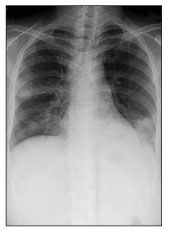

A chest radiograph and CT scan of the chest revealed infiltrates and adenopathies (Figures 1 and 2). A Gram stain of a sputum specimen revealed gram-positive filamentous rods (Figure 3). Bilateral pneumonia caused by N asteroides was diagnosed, and the patient was started on a regimen of ceftriaxone and trimethoprim/sulfamethoxazole (TMP/SMX), which resulted in significant improvement within a few days. Unfortunately, the patient signed out against medical advice and has been lost to follow-up.

Figure 1.Chest radiograph revealed left lower lobe, lingular, and right upper lobe infiltrates.